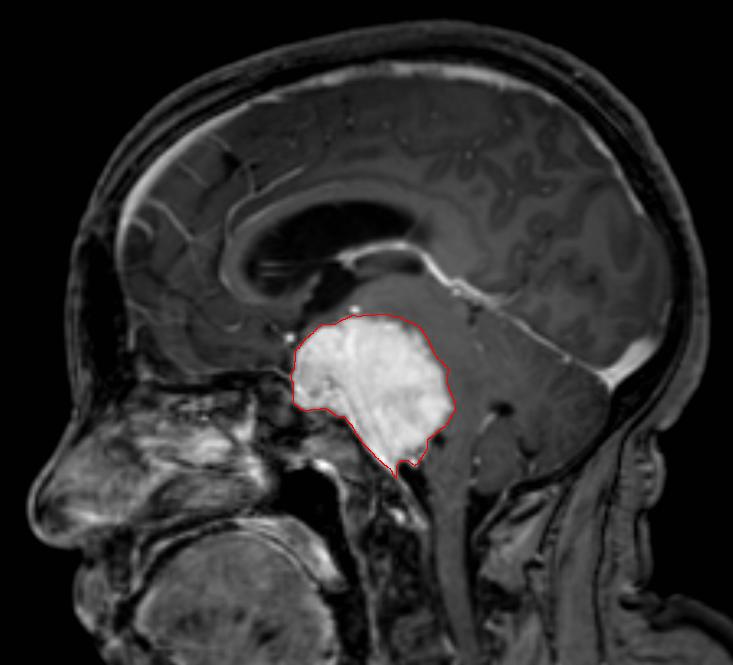

一个SCP-CN-2592-2接触者的脑部MRI扫描图

当任何人类直接接触到SCP-CN-2592-2时,该人员将于5-7小时内因颅内压过高和脑干机械性损伤而死亡,尸检表明其颅骨内存在一材质与SCP-CN-2592-2类似的不规则骨质球状物体。组织切片显示其周边脑组织存在大量浸润灶与根须状钙化结构,推测可能为SCP-CN-2592-2的繁殖方式。